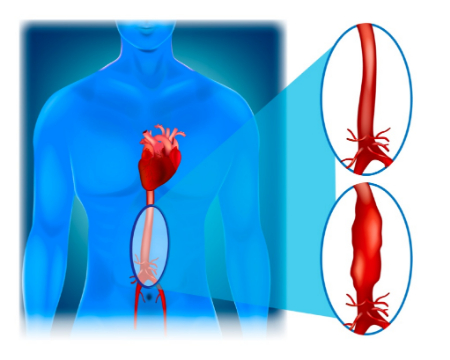

آنوریسم آئورت شکمی چیست؟

آنوریسم آئورت شکمی یک ناحیه بزرگ شده در قسمت پایین شریان اصلی بدن، به نام آئورت است. آئورت از قلب عبور کرده و از مرکز قفسه سینه و ناحیه شکم عبور می کند.

آئورت بزرگترین رگ خونی بدن است. پارگی آنوریسم آئورت شکمی می تواند باعث خونریزی تهدید کننده زندگی شود. درمان بستگی به اندازه آنوریسم و سرعت رشد آن دارد. درمان از چکاپ های سلامتی منظم و آزمایشات تصویربرداری تا جراحی اورژانسی متغیر است.